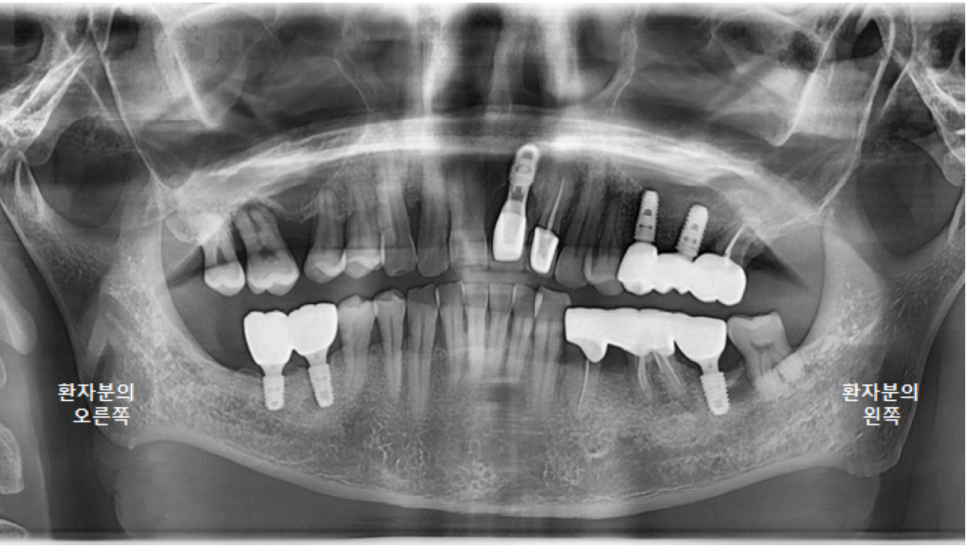

보철물을 다 붙이고 나서 촬영한 파노라마 엑스레이입니다.

앞니가 들어가서 심미적으로도 좋아졌고,

교합 평면도 좋아졌습니다.

이제 환자분의 식사가 조금 더 편해져서, 잘 드실 수 있게 되었습니다. ^^